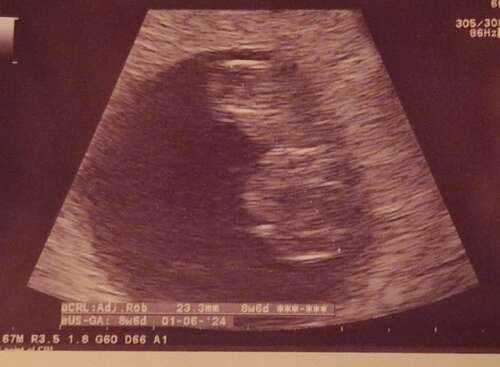

Hier afgelopen donderdag met 6+6 echo gehad, toen was alles goed. Netjes op termijn, sterk kloppend hartje etc.